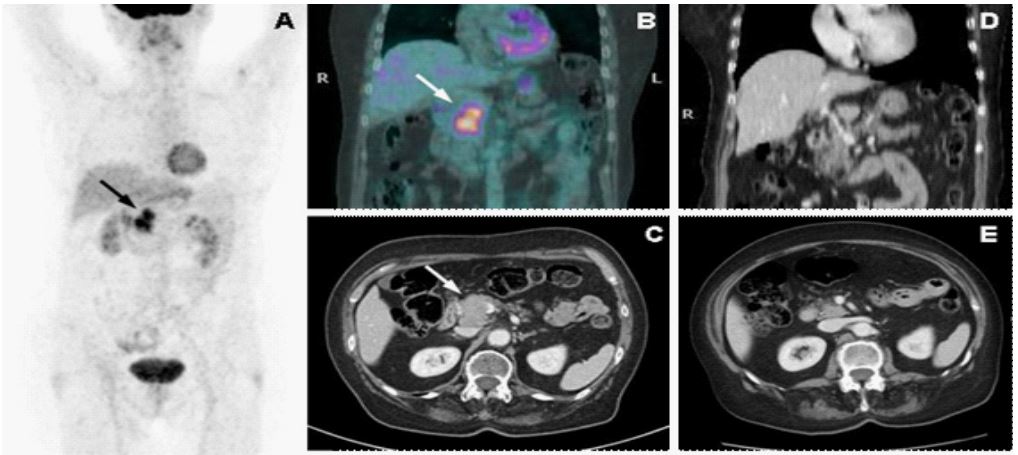

After thirteen months and four negative CT-scans, on May 2010 a new pancreatic lesion was observed (3.9 x 2.9 cm) at the CT-Scan, with a related uptake at the 18F-FDG-PET/CT (Figure 3. A, B and C). The patient was asymptomatic. To confirm the high suspicion of recurrence a pancreatic ultrasound-guided percutaneous biopsy was performed, which concluded for MCC. The pathologist reported positivity for cytocheratin-20, synaptophysin and focally chromogranin A; Ki-67 was 80%, pathological material was inadequate to detect MCpyV

Figure 3: A: Maximum intensity projection image at diagnosis. B: high uptake pancreatic lesion in 18F-FDG-PET/CT. C: pancreatic lesion in CT-Scan. D and E: pancreatic lesion complete response in CT-Scan after chemotherapy.

After a multidisciplinary discussion, due to the long disease-free survival and good tolerance, systemic chemotherapy with the same regimen was proposed and three cycles were administered. The subsequent CT-scan showed a RECIST-based complete response (Figure 3. D and E).